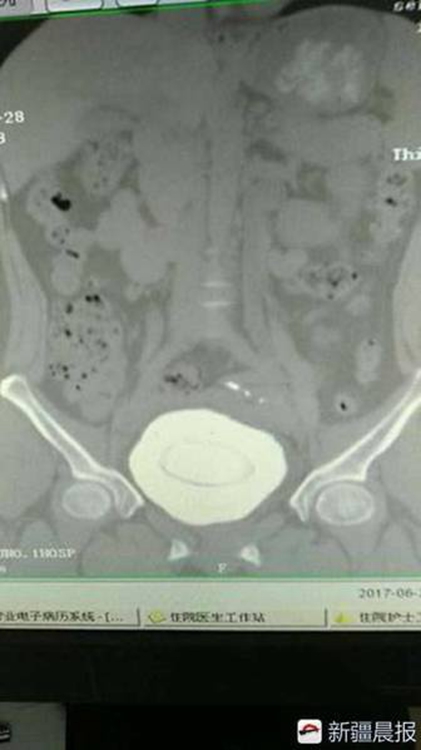

[??? ???? 7? 25?] ?? ??(新疆, ??) ???(阿克蘇, ???)? ?1?????? ?? ?? 1?? ????. ??? ?? ??? ???? ?? 10cm(760g)?? ??? ????? ???. ?? ??? ??? ??? ??? ??? ??? ?? ??? ???? ??.

?? ?? ??? ?? ? ?? “?? ??? ?? ??? ?? ?????. ?? ???? ?? ??? ???? ????? ????? ????. ??? ???? ?? ??? ??????”?? ???. ? ?? ?? ??? ??? ???? ?? ?? ????? ???? ??? ?? ??? ??? ?? ???? ??. ?? ??? ???? ???? ?? ???? ?? ??? ???? ??? ?? ????? ???? ??.

??? ??? ???? ?1?????? ???? ???? ?? ??? ??? ?? ??? ? ?? ??? ??? ????? ?? ?? ?? ???? ??. (??: ???)